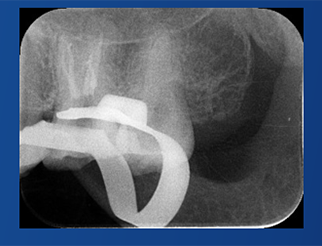

張云鳳老師案例